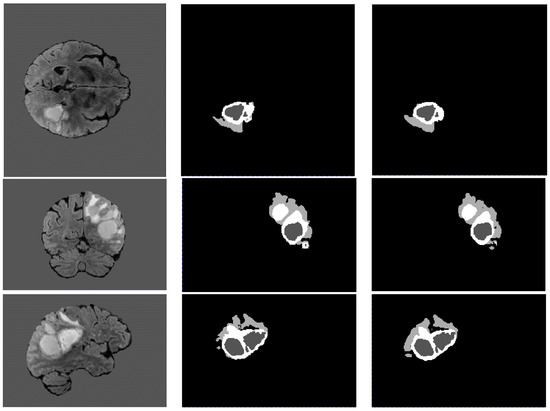

Figure 8 shows examples of the segmentation results obtained with the trained model on the BraTS 2021 dataset, with the coronal, sagittal, and horizontal planes in an order from top to bottom. From left to right are the T1 modality, the real label, and the segmentation results. From the segmentation results, it can be seen from Figure 8 that the segmentation results on the tumor core region are highly close to the ground truths with little amounts of error. However, in the enhanced tumor region (i.e., the white region), a certain amount of error exists in the coronal and sagittal planes. In addition, there is also a modest amount of error for the segmentation of the edema region (i.e., the light grey region). In general, the proposed approach is able to separate the tumor from the healthy region, and it retains more complete information from the tumor.

Figure 8. Examples of segmentation results using the Ga-U-Net model.